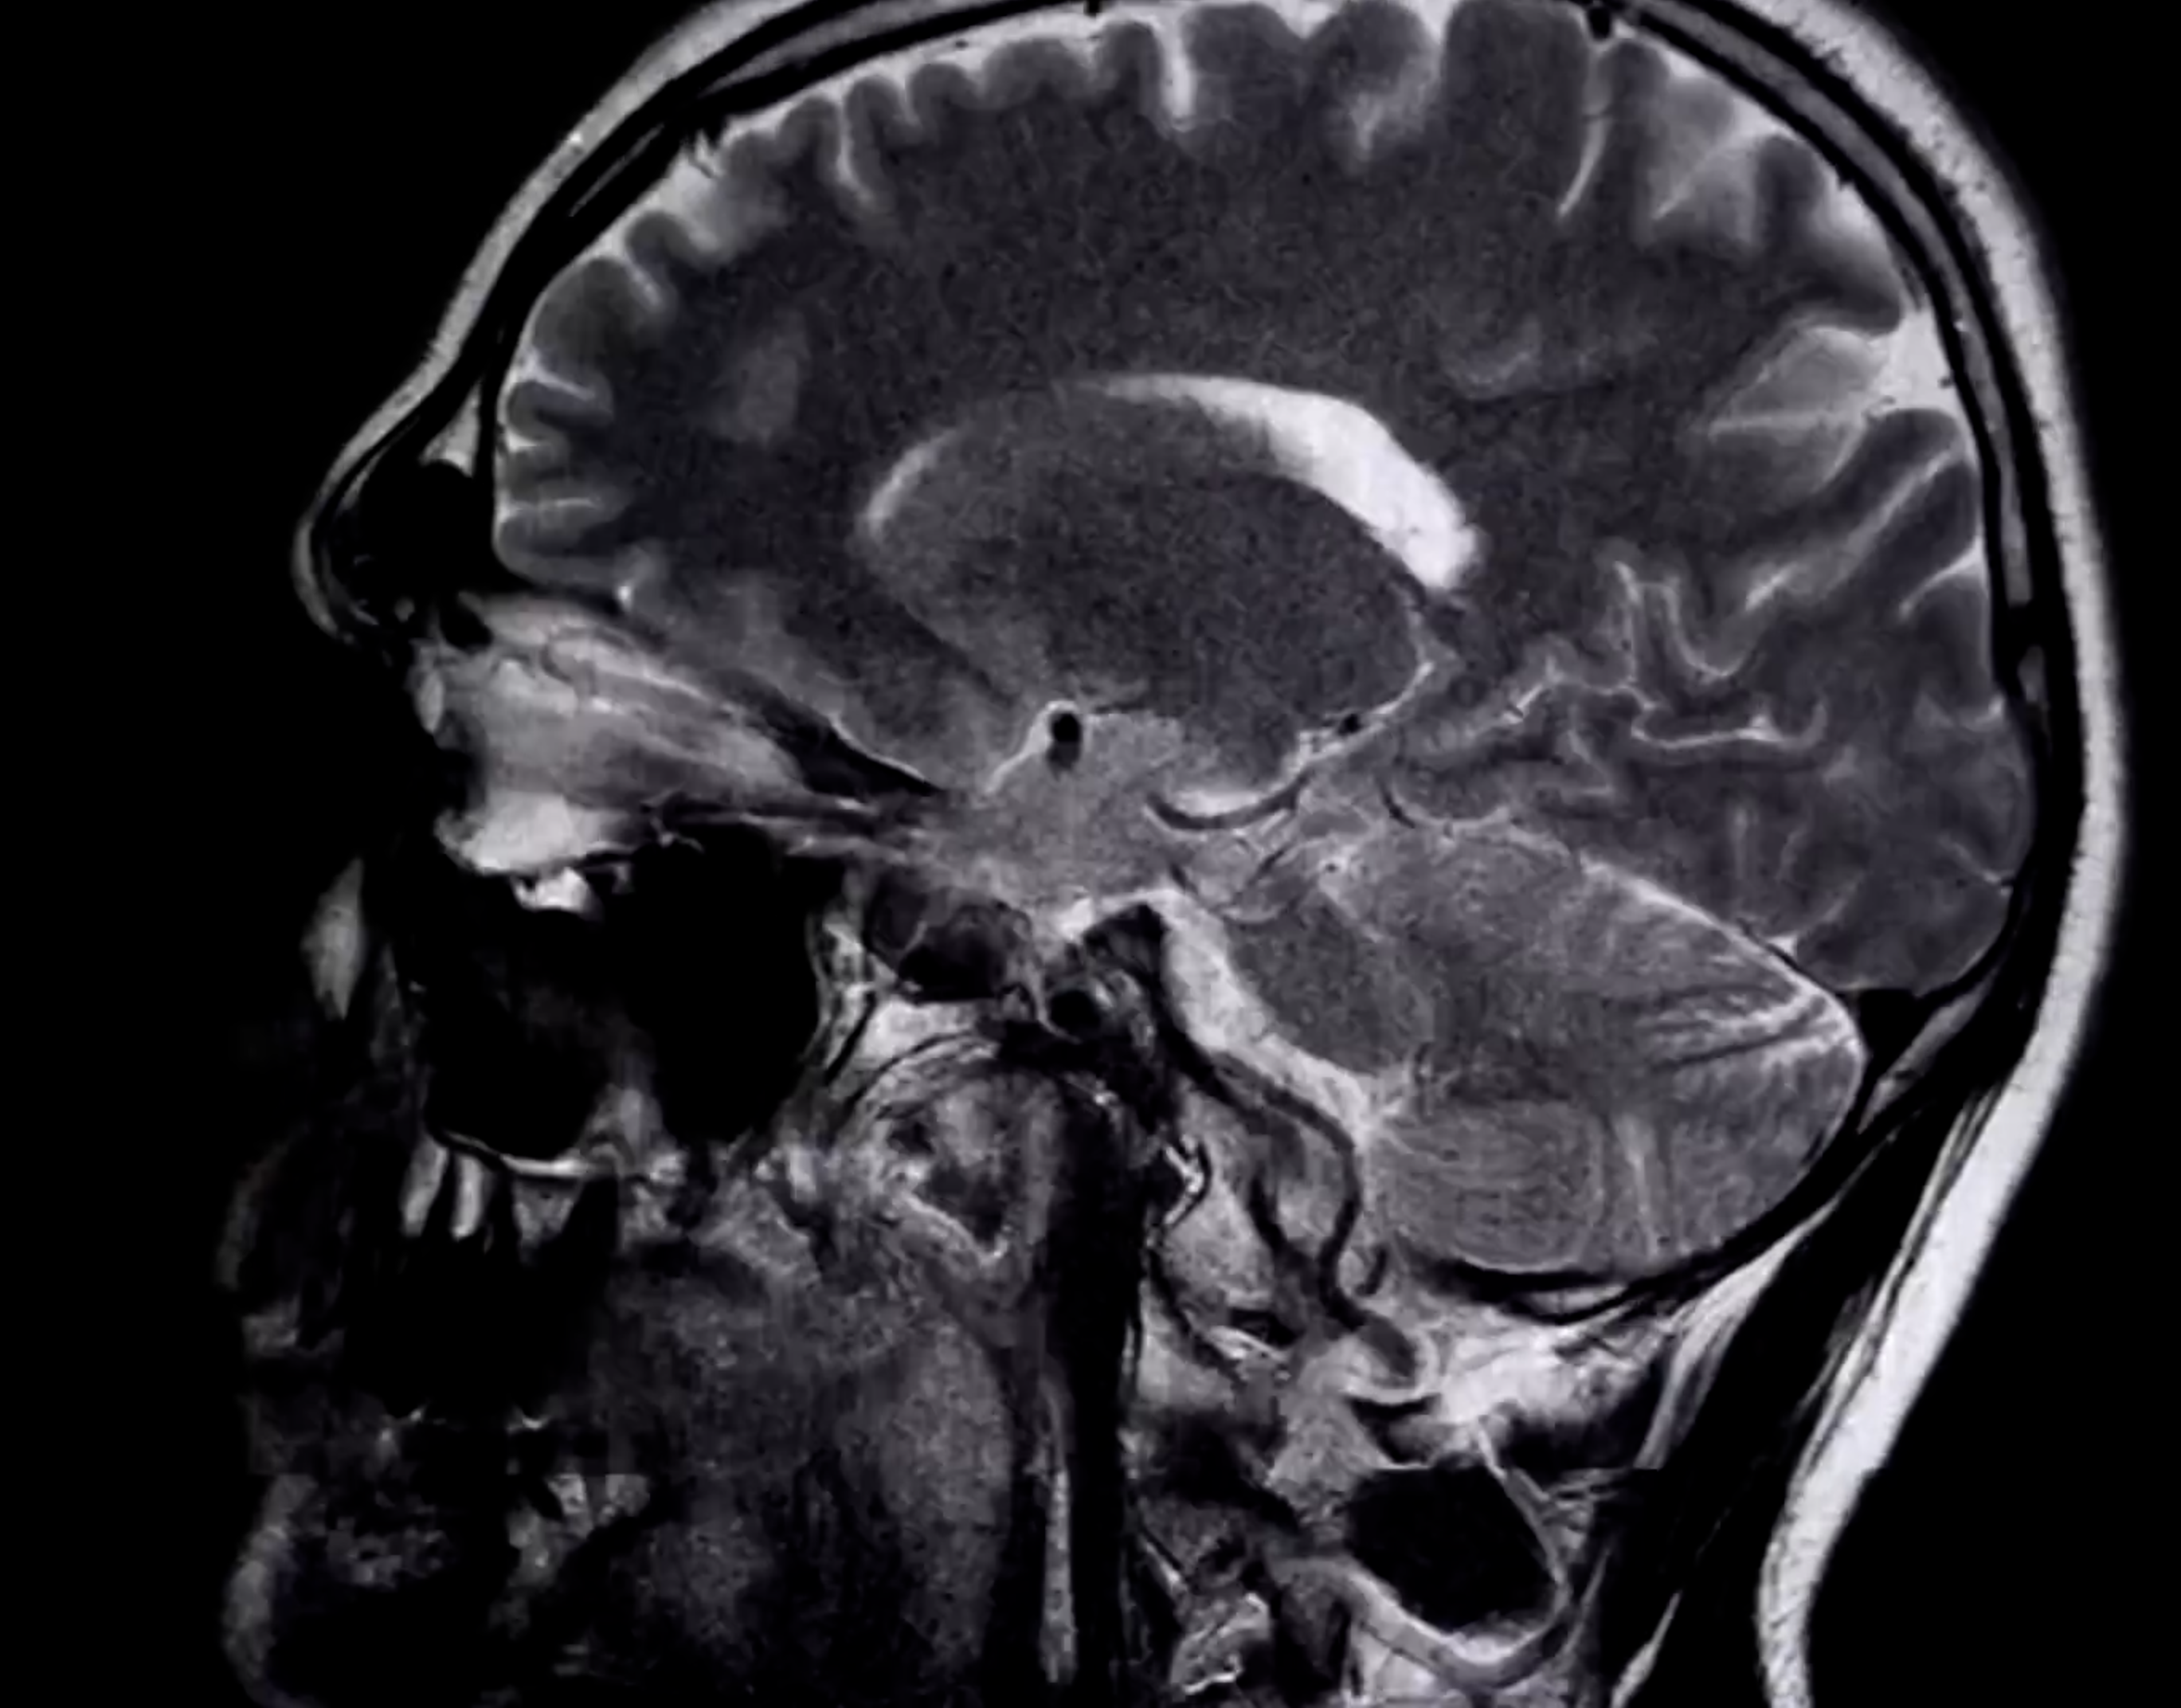

使用仪器观测的人脑图像